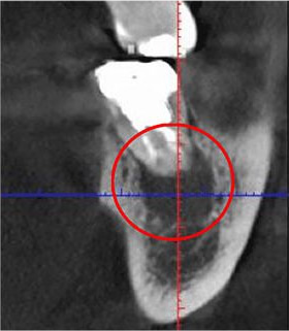

通常は「2次元」のレントゲンを使用して診断を行いますが、当院では「3次元」での撮影が可能なCTを用いることで、より詳細な診断を行います。

2次元と3次元では「見える範囲」が異なります。

下の画像は他の治療のケースですが、同じ部位を2次元レントゲン(左)と3次元CT(右)で撮影したものです。

丸がついている部分が問題のある部分で、3次元では黒い影がはっきり見えますが、2次元では確認できません。

簡単にまとめると、2次元レントゲンだけでは「問題が見落とされる」可能性があるということです。

歯科医療では、「見える」「見えない」が大きな違いを生みます。

当院では、しっかりとした視野を提供する3次元のCT装置を使って診断を行っています。